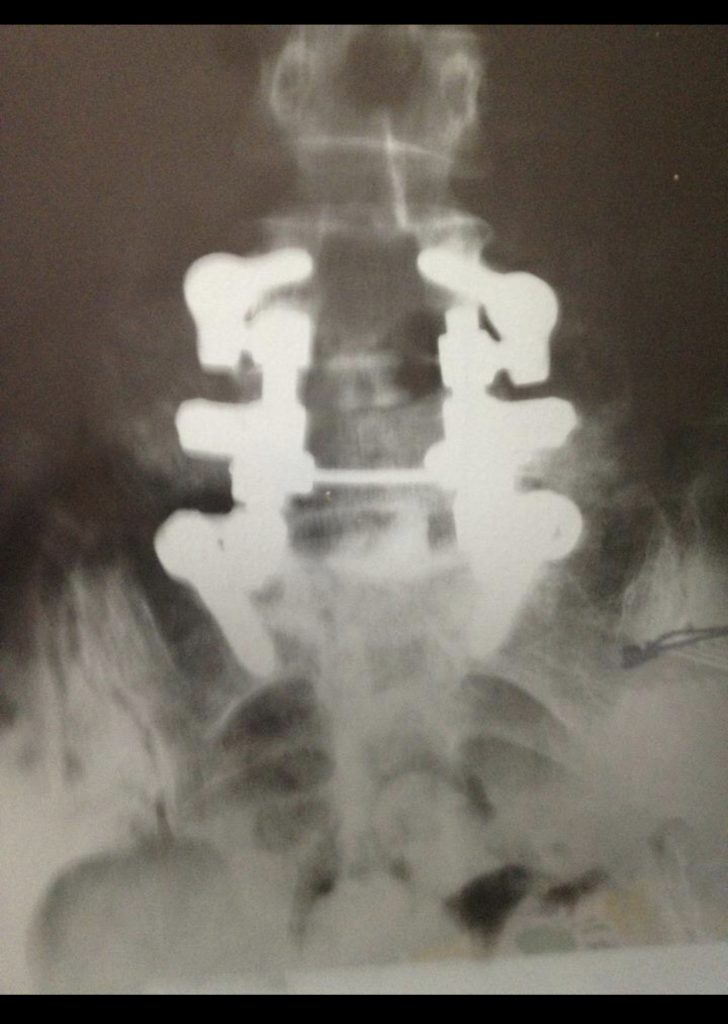

When I was 32, I was suffering from degenerative disc disease (DDD) and was a candidate for a double fusion. I searched for the best doctor in the US and found Dr. Frank Cammisa at HSS. He was extremely professional and knowledgeable! My fusion was expected to last 10 years, and I am on year 19. I highly recommend him for an advanced spine problem. His work is perfectionism at its finest! His talent let me raise my children almost pain-free along with enjoying many hobbies such as cycling! I was also able to conceive and have a beautiful healthy baby after my fusion!